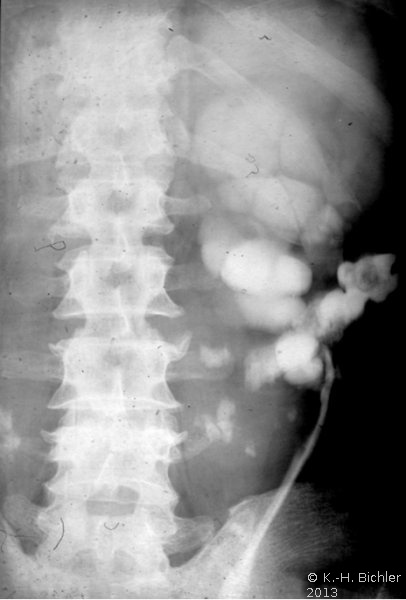

Die Hufeisenniere neigt aufgrund ihrer morphologischen Verhältnisse zu Harnstau, Harnwegsinfekt und daraus resultierend zur Harnsteinbildung, die zu erheblichen Komplikationen führen kann, wie in dieser Kasuistik gezeigt.

Der Patient kam mit Zeichen eines schweren, fieberhaften Harnwegsinfektes in unsere Behandlung. Die Diagnostik mit Sonographie und Ausscheidungsurogramm sowie Angiographie ergab eine ausgedehnte Harnsteinbildung beiderseits, wobei es im linken Nierenanteil zu Harnabflussbehinderungen gekommen war. Die Abbildungen zeigen die diagnostischen Maßnahmen. Der linke Nierenanteil wurde wegen erheblichen pyonephrotischem Umbau entfernt.